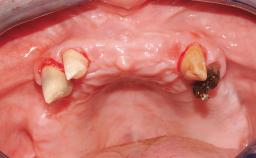

Conventional Loading of Eight Implants in the Maxilla and Final Restoration with a Full-Arch Gold-Ceramic FDP

A 35-year-old Caucasian female presenting with advanced periodontal disease involving both the maxillary and the mandibular dentition was referred for evaluation. The patient, a non-smoker in good general health, requested treatment for recurrent periodontal abscesses, tooth mobility, and discomfort during chewing, as well as restoration of her missing teeth with a fixed prosthesis to improve mastication and esthetics. All residual maxillary teeth exhibited plaque deposits, deep pockets, bleeding on probing, and class III mobility and were evaluated as hopeless. All residual mandibular teeth except tooth 37 could be maintained after periodontal therapy.

Bone Augmentation Horizontal|Staged|Vertical

Augmentation Materials Autogenous block(s)